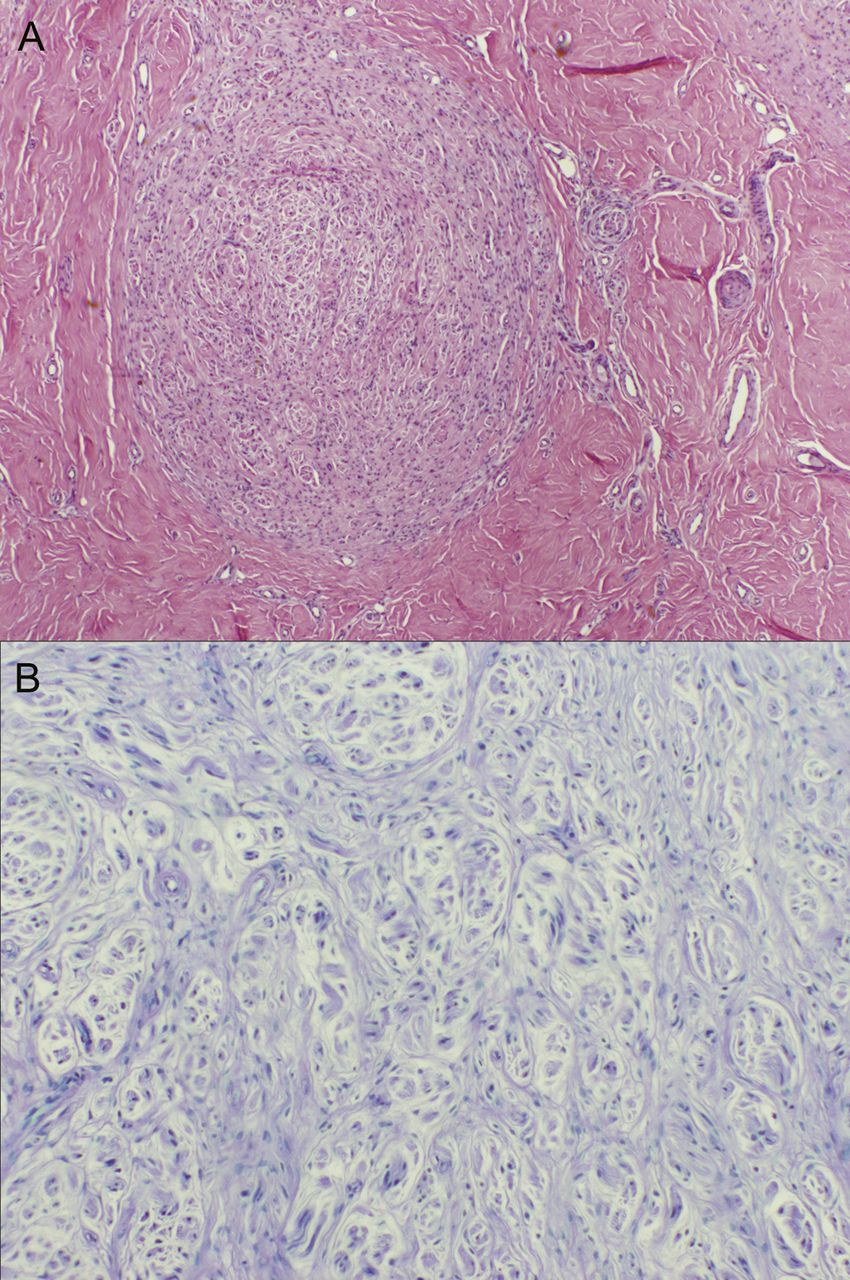

(A)左下肢MRI (T1序列)显示腓肠神经扩大(箭头)和轻度增强暗示领域活跃的炎性变化,减少信号符合疤痕。(B)超声显示的腓肠神经局部膨胀测量4.0毫米×8.0毫米(箭头所指)。